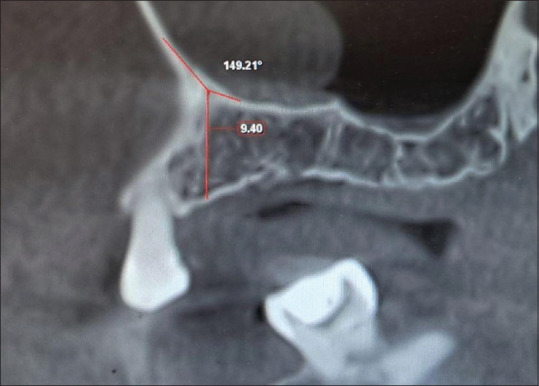

Background: Implant placement in the posterior maxilla is challenging in the case of maxillary sinus pneumatization. Increasing the vertical dimension by grafting the sinus floor is a common surgical modality. Cone-beam computed tomography (CBCT) scans are used to assess the presurgical anatomic variations of the maxillary sinus and determine the difficulty that might be encountered while performing sinus elevation. The sinus membrane is elevated from both the lateral and mesial walls of the sinus. The location and angulation of the palatal-nasal recess (PNR) on the medial wall of the sinus could complicate the elevation of the sinus membrane in this region. This study aimed to assess the angulation of the PNR and its position with respect to the alveolar crest in dentulous and edentulous subjects in the 1st molar region on CBCT scans.

Materials and methods: One hundred and fifty-two scans were selected from the department database. Sagittal sections including the 1st molar region were selected and measurements made. The PNR height was measured from the alveolar crest in millimeters and angulation in degrees and compared between the dentulous and edentulous groups.

Results: The dentulous group showed a statistically significant greater distance (10.4 ± 2.8 mm) between the alveolar crest and PNR as compared to the edentulous group (8.08 ± 3.1 mm). The edentulous group showed a statistically significant greater PNR angle (139.6o ± 13.6o) as compared to the dentulous group (133.4o ± 16.4o).